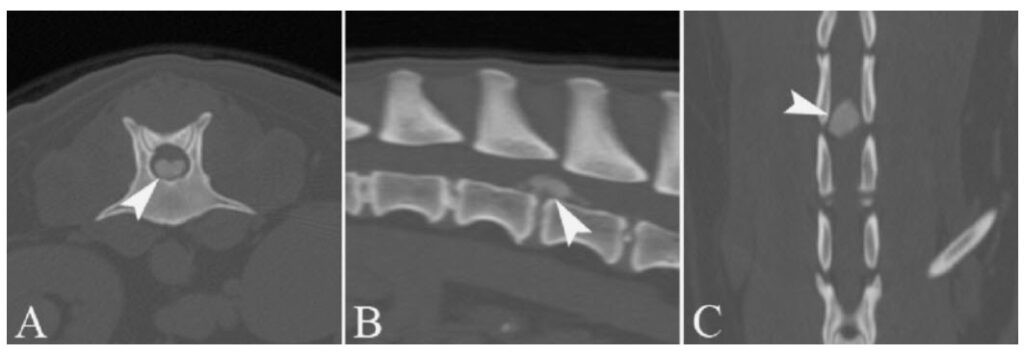

では、「犬の椎間板ヘルニア」とは、具体的にどんな病気なのでしょうか? この病気を説明するには、椎間板の説明をする必要があります。 まず、「椎間板」とは、一般的に犬の背骨と背骨の間にクッションのように挟まっている「クッション材のような組織」の事を言います。 そして、「ヘルニア」とは、そのクッション材が、何らかの原因で「グシャ」っと潰れて変形してしまっ 犬の椎間板ヘルニアで針治療について検討されている方は、参考にしてください。 そもそも針治療って何をしているの? 第一段階 まず深い部分のコリをほぐす 第二段階 マヒした部分の「目を覚ます」 最終段階 体を動かす感覚を取り戻す。 犬の椎間板椎間板ヘルニア(胸腰椎) >>>犬の胸腰部の椎間板ヘルニアとは? 正常な 椎間板 は左下の図のように 椎骨 (背骨)の骨と骨の間に存在し、中心にあるゼリー状の 髄核 と、この 髄核 を取り巻く 線維輪 で構成されており、背骨に加わる圧力を吸収

椎間板ヘルニアの治療 椎間板ヘルニアの治療は大きく分けて内科療法と外科療法に分けられます。 内科療法 内科療法は脊髄の圧迫の軽度な子、症状の軽い子に対しておこなわれます。ただし、ダックスのような軟骨異 犬の神経疾患でも最も多いのが 椎間板ヘルニアです。 症状は、痛みや後ろ足のふらつきなど の軽いものから、自力で立ち上がる ことができなくなる重症のものなど さまざまです。 治療法についてはグレ